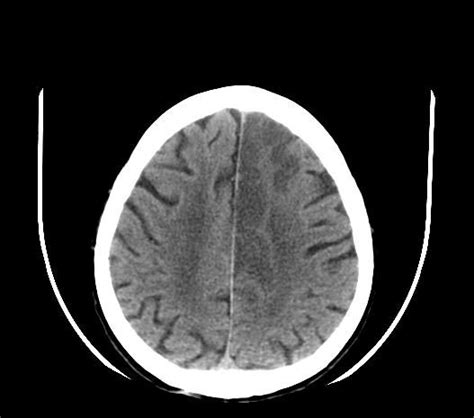

What Does a CT Scan Show in Ischemic Stroke?

In the early stages of an ischemic stroke , a CT scan might not show anything obvious. This is because it takes time for the brain tissue to change in a way that’s visible on a CT scan . However, there are subtle signs that radiologists (doctors who specialize in interpreting medical images) look for.

One of the earliest signs is called the “dense artery sign.” This is when a blood clot is seen directly within an artery in the brain. Another early sign is blurring of the gray-white matter interface. This means the normal distinction between the gray matter (the outer layer of the brain) and the white matter (the inner layer) becomes less clear. As time passes, the CT scan will show more obvious changes. The affected area of the brain may appear darker than the surrounding tissue. This is because the damaged brain tissue is less dense due to swelling and cell death. Eventually, the CT scan can show a clear area of infarction, which is the area of brain tissue that has died due to lack of blood flow.

It’s important to remember that the appearance of an ischemic stroke on a CT scan changes over time. What might be subtle in the first few hours can become much more obvious later on. That’s why radiologists often compare current CT scans with previous ones, if available, to look for any changes. The information from the CT scan is used to determine the extent of the stroke and guide treatment decisions.